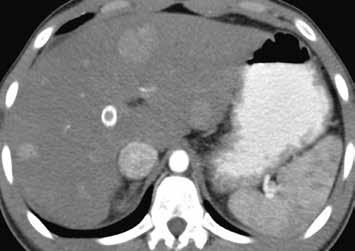

Nativně na CT je nezřetelně naznačeno několik hypodenzních ložisek (17). Všechna se vcelku homogenně sytí v arteriální fázi (18). V portovenózní fázi je sycení jater celkově nehomogenní, ložiska jsou však nadále lehce hyperdenzní oproti okolnímu parenchymu jater (19).